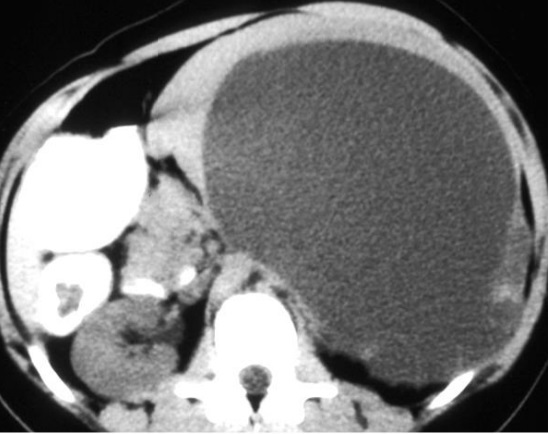

Image radiologique TDM une

splenomegalie par infection mononucleose . La rate

est volumineuse , tres epais , sa diamètre

antero-posterieure depasse plus de 10,5cm |